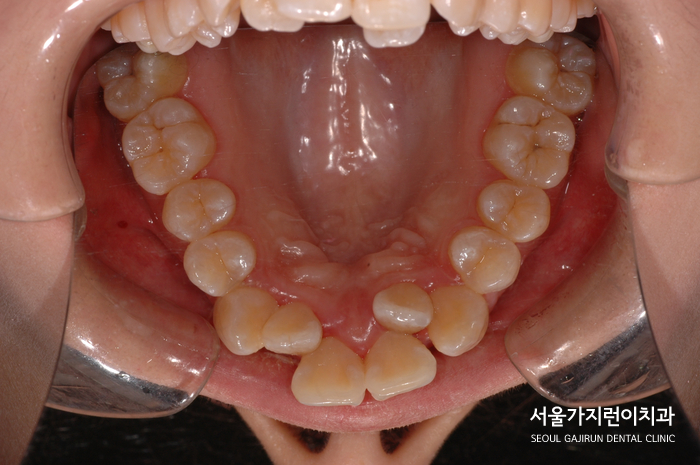

환자 분의 경우 덧니 양상이 명확히 나타난 케이스로 치아의 크기 대비 공간이 부족해 덧니화 된 경우인데요. 치아 배열이 상당히 흐트러진 경우로 정중선이 어긋나 있고 송곳니에서부터 불규칙한 교합 관계가 보여 상악 치아가 앞으로 쏠려 있는 기울어짐을 확인할 수 있었어요. 이렇게 되면 입술도 앞으로 밀려나와 돌출입처럼 보이게 되는데요. 때문에 치열을 바로 잡고 입술의 위치가 자연스럽게 뒤로 들어갈 수 있도록 돌출된 입도 교합을 찾을 필요가 있었어요.

그래서 환자분의 경우 악궁이 좁아보이는 것을 확인해 발치를 진행해 공간을 확보하고 악궁을 넓히면서 자연스러운 아치 모양이 되도록 교정치료를 진행했습니다. 발치 교정을 진행했을 때는 어금니가 앞으로 끌려오지 못하도록 구개유지장치를 사용했는데요. (TPA), 발치 공간의 경우 앞니 쪽에서 제대로 닫게 하고 안정적인 교정결과를 위해 수술하지 않고도 치아이동을 이끌어냈습니다.